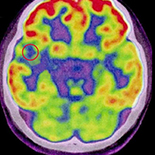

Dynamic Contrast-Enhanced Magnetic Resonance Imaging (DCE-MRI) Combined with Positron Emission Tomography-Computed Tomography (PET-CT) and Video-Electroencephalography (VEEG) Have Excellent Diagnostic Value in Preoperative Localization of Epileptic Foci in Children with Epilepsy

A total of 166 children with epilepsy undergoing preoperative DCE-MRI, VEEG, and PET-CT examinations, surgical resection of epileptic foci, and intraoperative electrocorticography (ECoG) monitoring were enrolled. All children were followed up for 12 months and grouped by Engles prognostic classification for epilepsy. Based on intraoperative ECoG as gold standard, the diagnostic values of DCE-MRI, VEEG, PET-CT, DCE-MRI combined with VEEG, DCE-MRI combined with PET-CT, and combined application of DCE-MRI, VEEG, and PET-CT in preoperative localization for epileptic foci were evaluated.

The sensitivity of DCE-MRI, VEEG, and PET-CT was 59.64%, 76.51%, and 93.98%, respectively; the accuracy of DCE-MRI, VEEG, PET-CT, DCE-MRI combined with VEEG, and DCE-MRI combined with PET-CT was 57.58%, 67.72%, 91.03%, 91.23%, and 96.49%, respectively. Localization accuracy rate of the combination of DCE-MRI, VEEG, and PET-CT was 98.25% (56/57), which was higher than that of DCE-MRI combined with VEEG and of DCE-MRI combined with PET-CT. No statistical difference was found in the accuracy rate of localization between these three combined techniques. During the 12-month follow-up, children were grouped into Engles grade I (n=106), II (n=31), III (n=21), and IV (n=8) according to postoperative conditions.

All DCE-MRI combined with VEEG, DCE-MRI combined with PET-CT, and DCE-MRI combined with VEEG and PET-CT examinations have excellent accuracy in preoperative localization of epileptic foci and present excellent postoperative efficiency, suggesting that these combined imaging methods are suitable for serving as the reference basis in preoperative localization of epileptic foci in children with epilepsy.